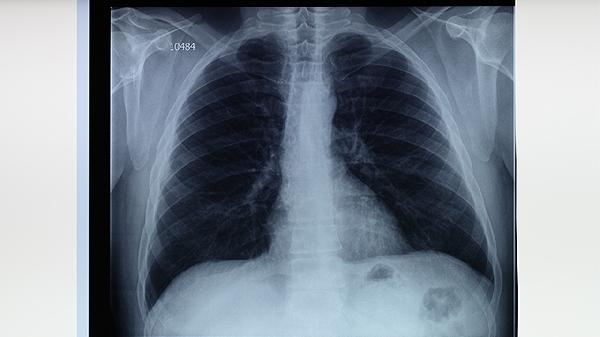

医生:一旦被查出肺癌,8件事万万不能再做了,小心病症迅猛恶化